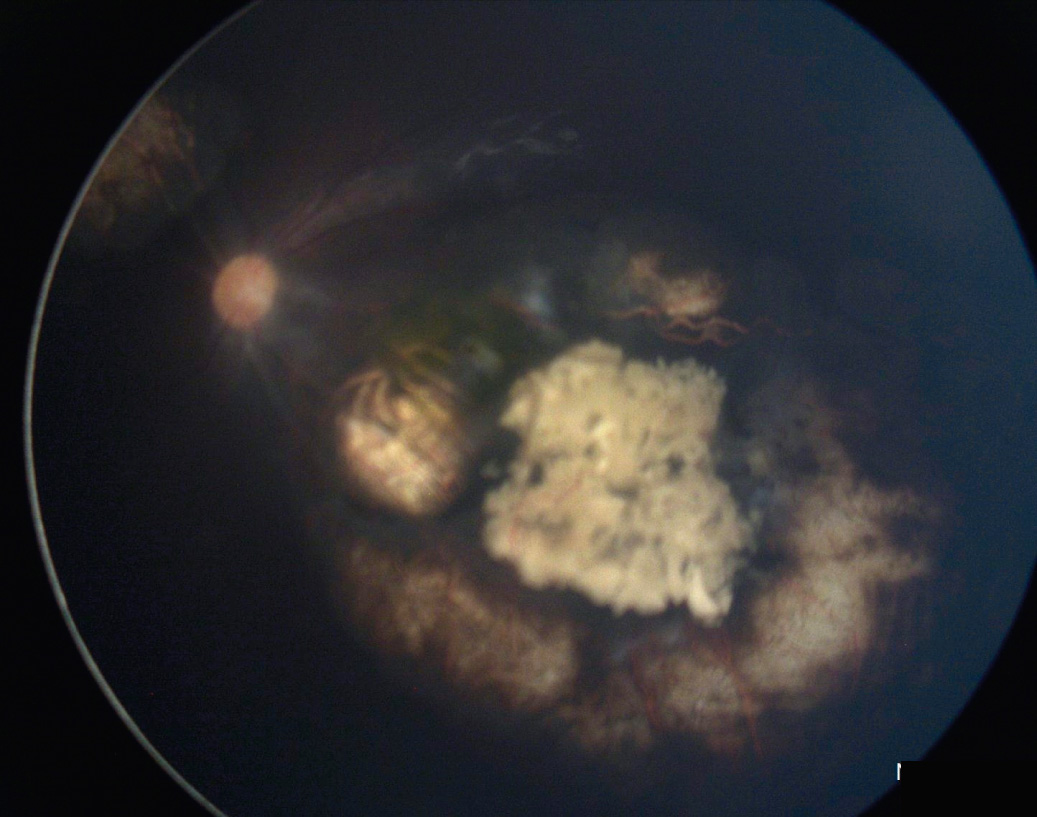

RET CAM

Cámara digital de contacto, de altísima precisión y resolución, que permite obtener imágenes de 130° de amplitud de la retina de prematuros y recién nacidos.

- Fondo de Ojo

- Foto de ángulo